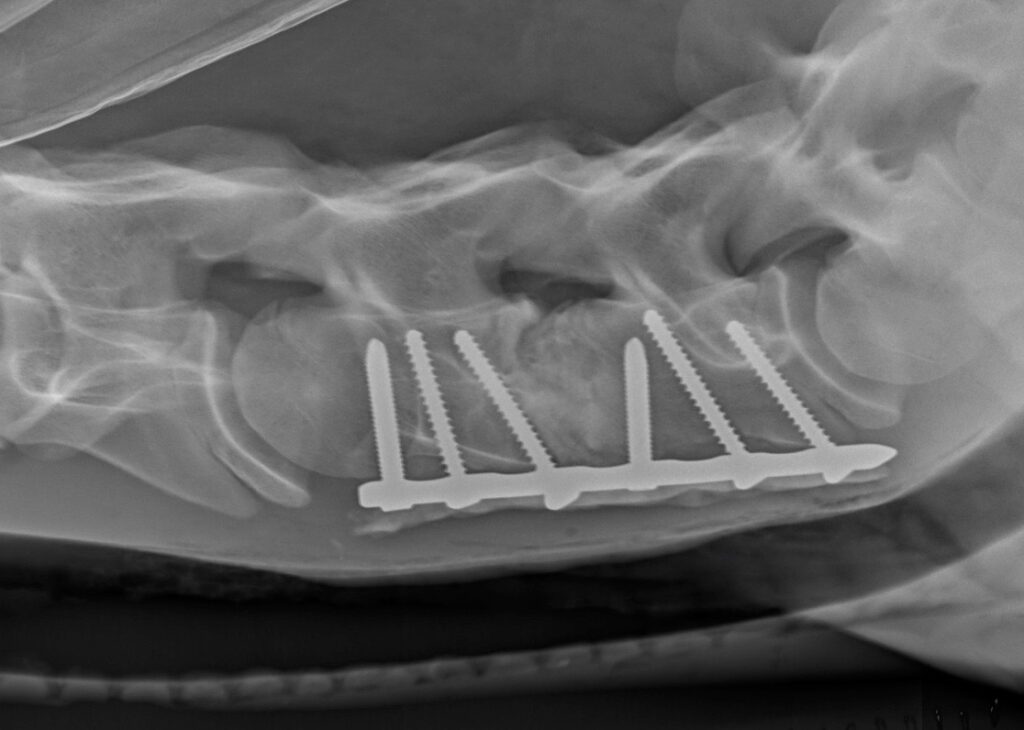

Obrázek 2c: Postižená kost a meziobratlová ploténka byly chirurgicky odstraněny a oba obratle byly spojeny pomocí ploténky a šroubů